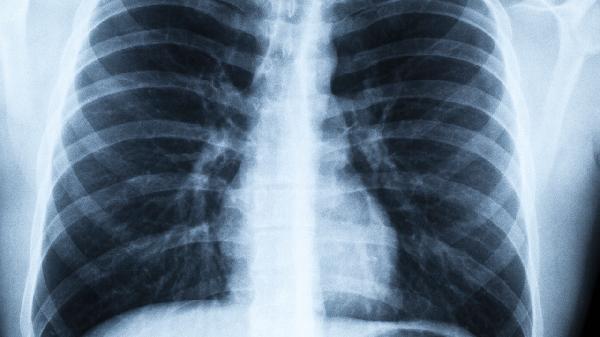

保護肺部健康需要從生活細節入手。除了遠離煙草,更要警惕這些容易被忽視的”隱形殺手”。建議每年進行一次低劑量螺旋CT檢查,這是目前篩查早期肺癌最有效的方法。記住,預防永遠比治療更重要,今天開始就給自己的呼吸系統多一些關愛吧。